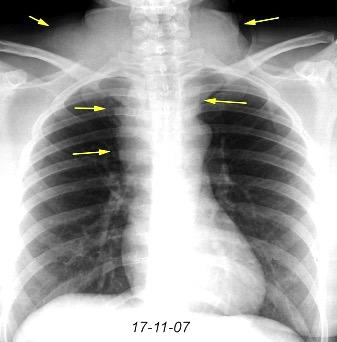

Triada de Garland

Ganglios paratraqueales derechos e hiliares bilaterales

95% de pacientes tienen ganglios hiliares bilaterales aislados o con afectación mediastínica (espec. paratraqueal derecho).

Criado E et al. Pulmonary sarcoidosis: typical and atypical manifestations at high-resolution CT with pathologic correlation. Radiographics. 2010